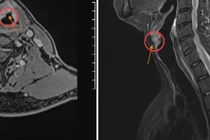

Khàn giọng tưởng hút thuốc, nói nhiều không ngờ ung thư thanh quản

90% trường hợp ung thư thanh quản là do thuốc lá. Nguy cơ mắc cao gấp 20 lần đối với người đang hút thuốc, gấp 40 lần đối với người hút thuốc nhiều.

Ông Sang, 53 tuổi, vừa phát hiện ung thư thanh quản giai đoạn muộn, bác sĩ chỉ định cắt bán phần dây thanh, bảo tồn chức năng nói.

Khàn tiếng kéo dài phát hiện ung thư thanh quản giai đoạn cuối